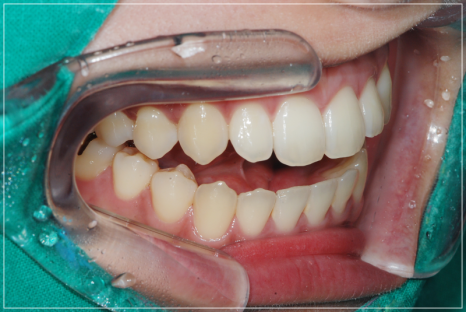

가지런히 정돈된 치열과 개방교합이 개선된 모습

또한, 단지 트랙션만 진행하는 것과는 달리

보다 안정적인 과정으로 대부분 일정하게

개선이 가능하다는 장점이 있는데요.

단지 트랙션만 진행하는 것과 달리

치아 교정을 먼저 진행해야 하는 만큼

시간과 노력을 들여야 하기에

번거로움이 있을 수 있지만,

보다 안전하게 진행이 가능하여

턱관절도 안정시킬 수 있으며,

대부분 일정하게 개선이

가능하다는 장점이 있습니다.